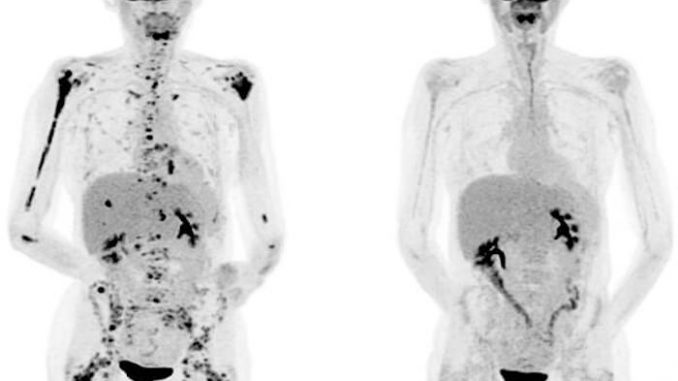

CART T-cell therapy eradicates tumors in nearly all patients with chronic lymphocytic leukemia (CLL) who had exhausted other treatment options, researchers at the Fred Hutchinson Cancer Research Center have reported.

It wasn’t until the second patient, Doug Olson, who received his CAR T cells about six weeks after Ludwig, that Porter had a eureka moment. When he received the call that Olson was also running a high fever, having trouble breathing and showing abnormal lab results, Porter realized that these were signs that the treatment was working. “It happens when you kill huge amounts of cancer cells all at the same time,” Porter says. What threw him off initially is that it’s rare for anything to wipe out that much cancer in people with Ludwig’s and Olson’s disease. June and Porter have since calculated that the T cells obliterated anywhere from 2.5 lb. to 7 lb. of cancer in Ludwig’s and Olson’s bodies. “I couldn’t fathom that this is why they both were so sick,” says Porter. “But I realized this is the cells: they were working, and working rapidly. It was not something we see with chemotherapy or anything else we have to treat this cancer.”

Ludwig has now been in remission for seven years, and his success led to the larger study of CAR T cell therapy in children like Kaitlyn, who no longer respond to existing treatments for their cancer. The only side effect Ludwig has is a weakened immune system; because the treatment wipes out a category of his immune cells–the ones that turned cancerous–he returns to the University of Pennsylvania every seven weeks for an infusion of immunoglobulins to protect him from pneumonia and colds. Olson, too, is still cancer-free.